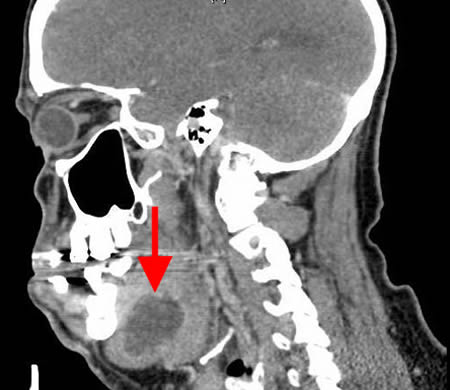

Sagittal CT scan with contrast showing submandibular space abscess

From the personal collection of Melanie S. Lang and Thomas B. Dodson